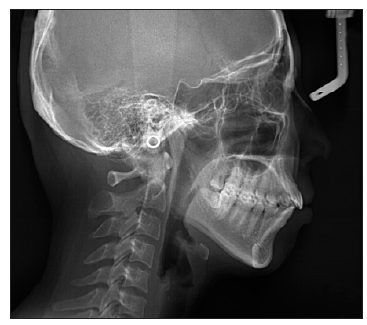

图 14

治疗前头侧位片"